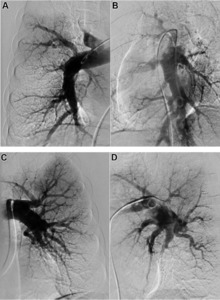

Both V/Q scanning and modern multidetector CT angiography (CTPA) may be accurate methods for the detection of CTEPH, with excellent diagnostic efficacy in expert hands (sensitivity, specificity, and accuracy of 100%, 93.7%, and 96.5% for V/Q and 96.1%, 95.2%, and 95.6% for CTPA).[9] However, CTPA alone cannot exclude the disease, but may help identify pulmonary artery distension resulting in left main coronary artery compression, pulmonary parenchymal lesions (e.g. as complications from previous pulmonary infarctions), and bleeding from bronchial collateral arteries.[10] Today, the gold standard imaging remains invasive pulmonary angiography (PAG) using native angiograms or a digital subtraction technique.